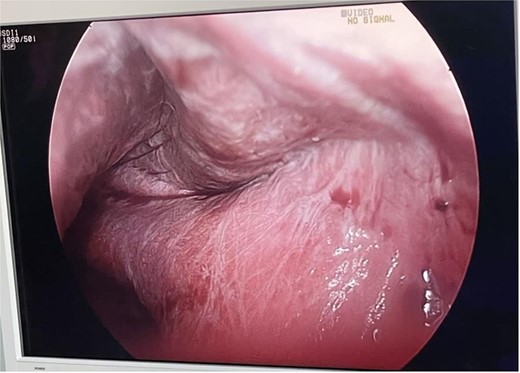

The patient was in the supine position (American position) and a Veress needle was inserted through a subumbilical skin incision and a pneumoperitoneum was created to 13 mmHg, after which a 10 mm optic trocar was inserted. Under optical control, another 5 mm trocar was inserted subxiphoidally and one 5 mm on the right mid-axillary line subcostally. Intraoperatively, a small whitish ribbon-like area was visualized in the area of the IVB segment with a length of ⁓3 cm/d. Using LigaSure, the Falciform ligament was resected for better visualization. Using a hook, the capsule of the cyst was opened and serous fluid was evacuated, which proved to be a simple cyst (Fig. 2). Cyst walls were excised down to the parenchyma using LigaSure. The cyst was visualized inside to rule out communication with the bile duct (Fig. 3). Due to the depth and intraparenchymal location, a drain was placed inside, which was removed on the 20th postoperative day until the drainage from the drain stopped completely. The total operative time was 40 min and the patient was discharged with a drain on the 2nd postoperative day. Pathomorphological examination of the removed cyst wall proved a simple cyst.